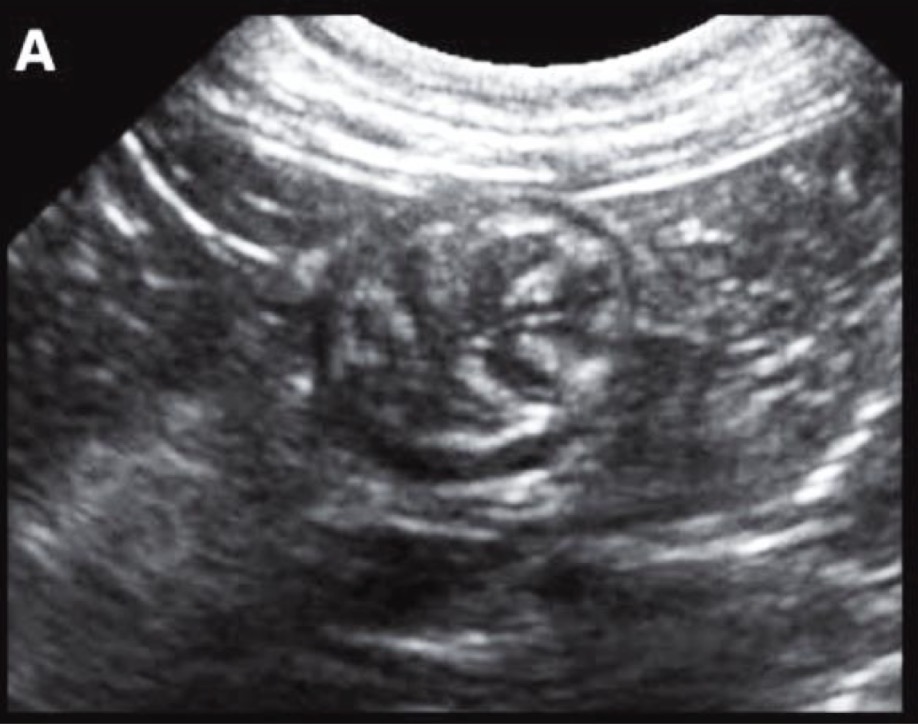

bullseye

What shape does intussusception of the bowel often take the shape of on an ultra sound?

Intussusception of the small intestine

What anomaly are these arrows pointing to?